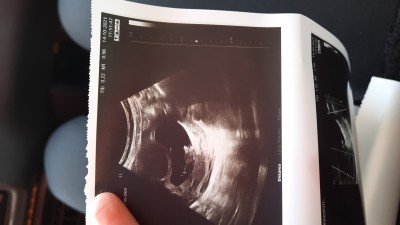

Gebelik dışında kimse yorum yapmıyor keselerimiz benzeyen veya anlayan varsa cinsiyet yazabilir mi:)) çok bilmiş kişiler zaten öğreneceksiniz gibi şeyler yazmasın insan 2.

bebeğini merak edemez mi.

Gebelik haftası 9+2

Erkek kesesi böyle oluyor diyorlar Allah gönlünüzdekini nasip etsin

Erkek bebekse fasülye seklinde kızsa yuvarlak diyorlar benimde gerçekten kızlarda yuvarlaktı şimdi fasülye gibi

Kese erkeğe benziyor

Kese şekline göre cinsiyet belli olsaydı bence Doktorlar da erkenden söylerdi kız veya erkek olduğunu alakası yok  milletin uydurması canım Rabbim gönlüne göre versin inşallah sağlıkla

Benim de 9.haftadayken kesem ultrason görüntüsü bu şekildeydi şimdi 12haftalik oldum ve doktorum 2 gun önce kız dedi cinsiyetine

Bana böyle kese fasulye kesin erkek dediler kız bebeğe hamileyim